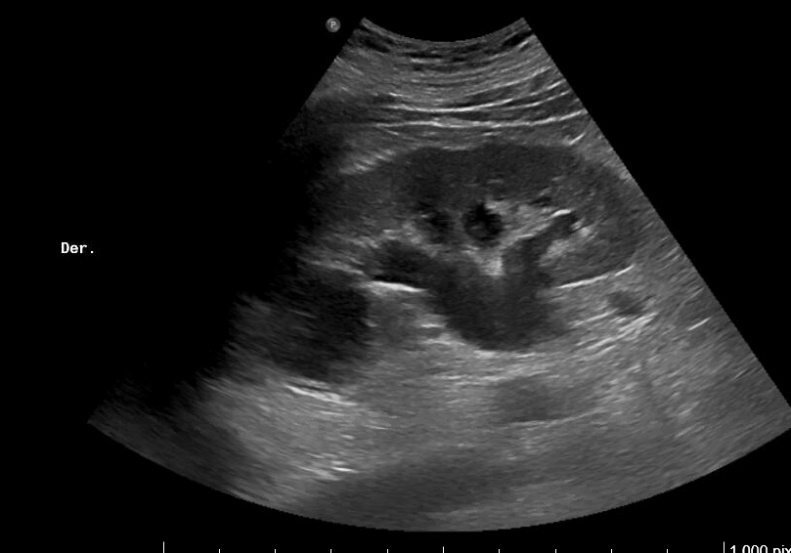

Imagen 1. Riñón derecho: hidronefrosis grado II. Tamaño 11.2 cm.

Imágenes 2 y 3. Riñón izquierdo: hidronefrosis grado II. Disminución del grosor cortical. Tamaño 11.5 cm.